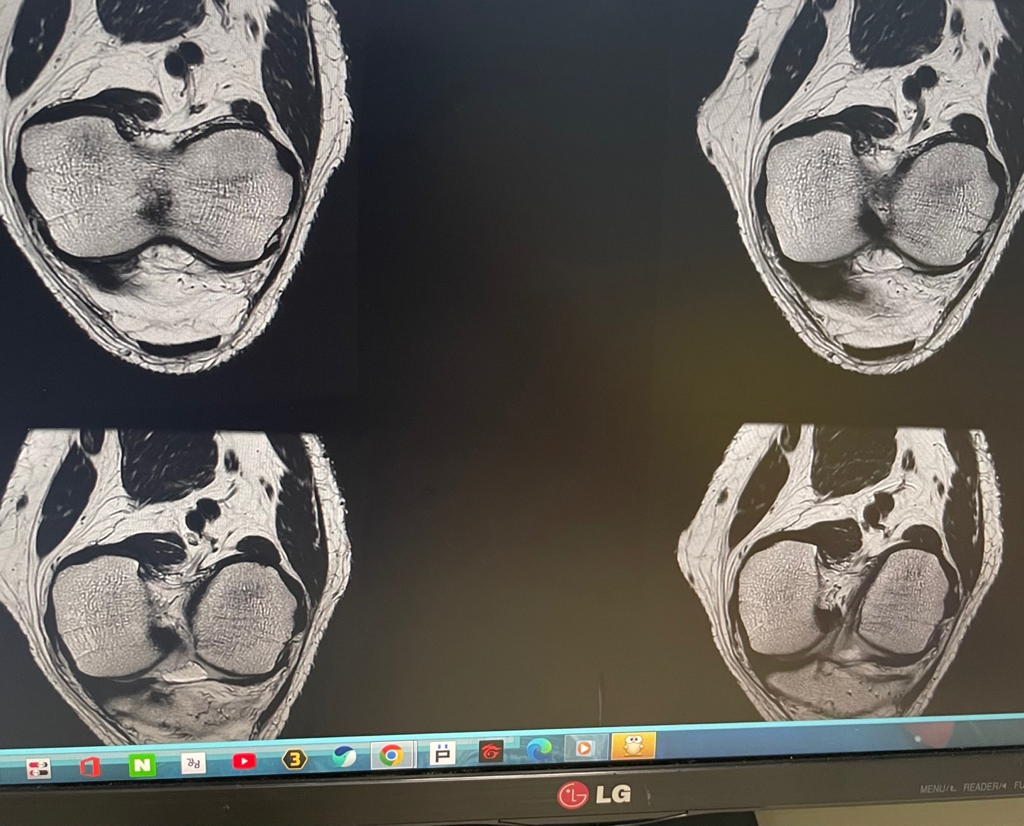

무릎 mri 원형원골인지 봐주실 수 있을까요

무릎이 너무 자주 아파서 mri를 찍어봤는데 무릎 연골에 이상이 있을까요

무릎이 선천적으로 원형연골인지 봐주시면 감사하겠습니다

• 1번 째 사진

MRI 판독에는 퇴행성 연골 손상, 바깥쪽 원판형 반월상 연골 이 의심된다고 적혀 있습니다.